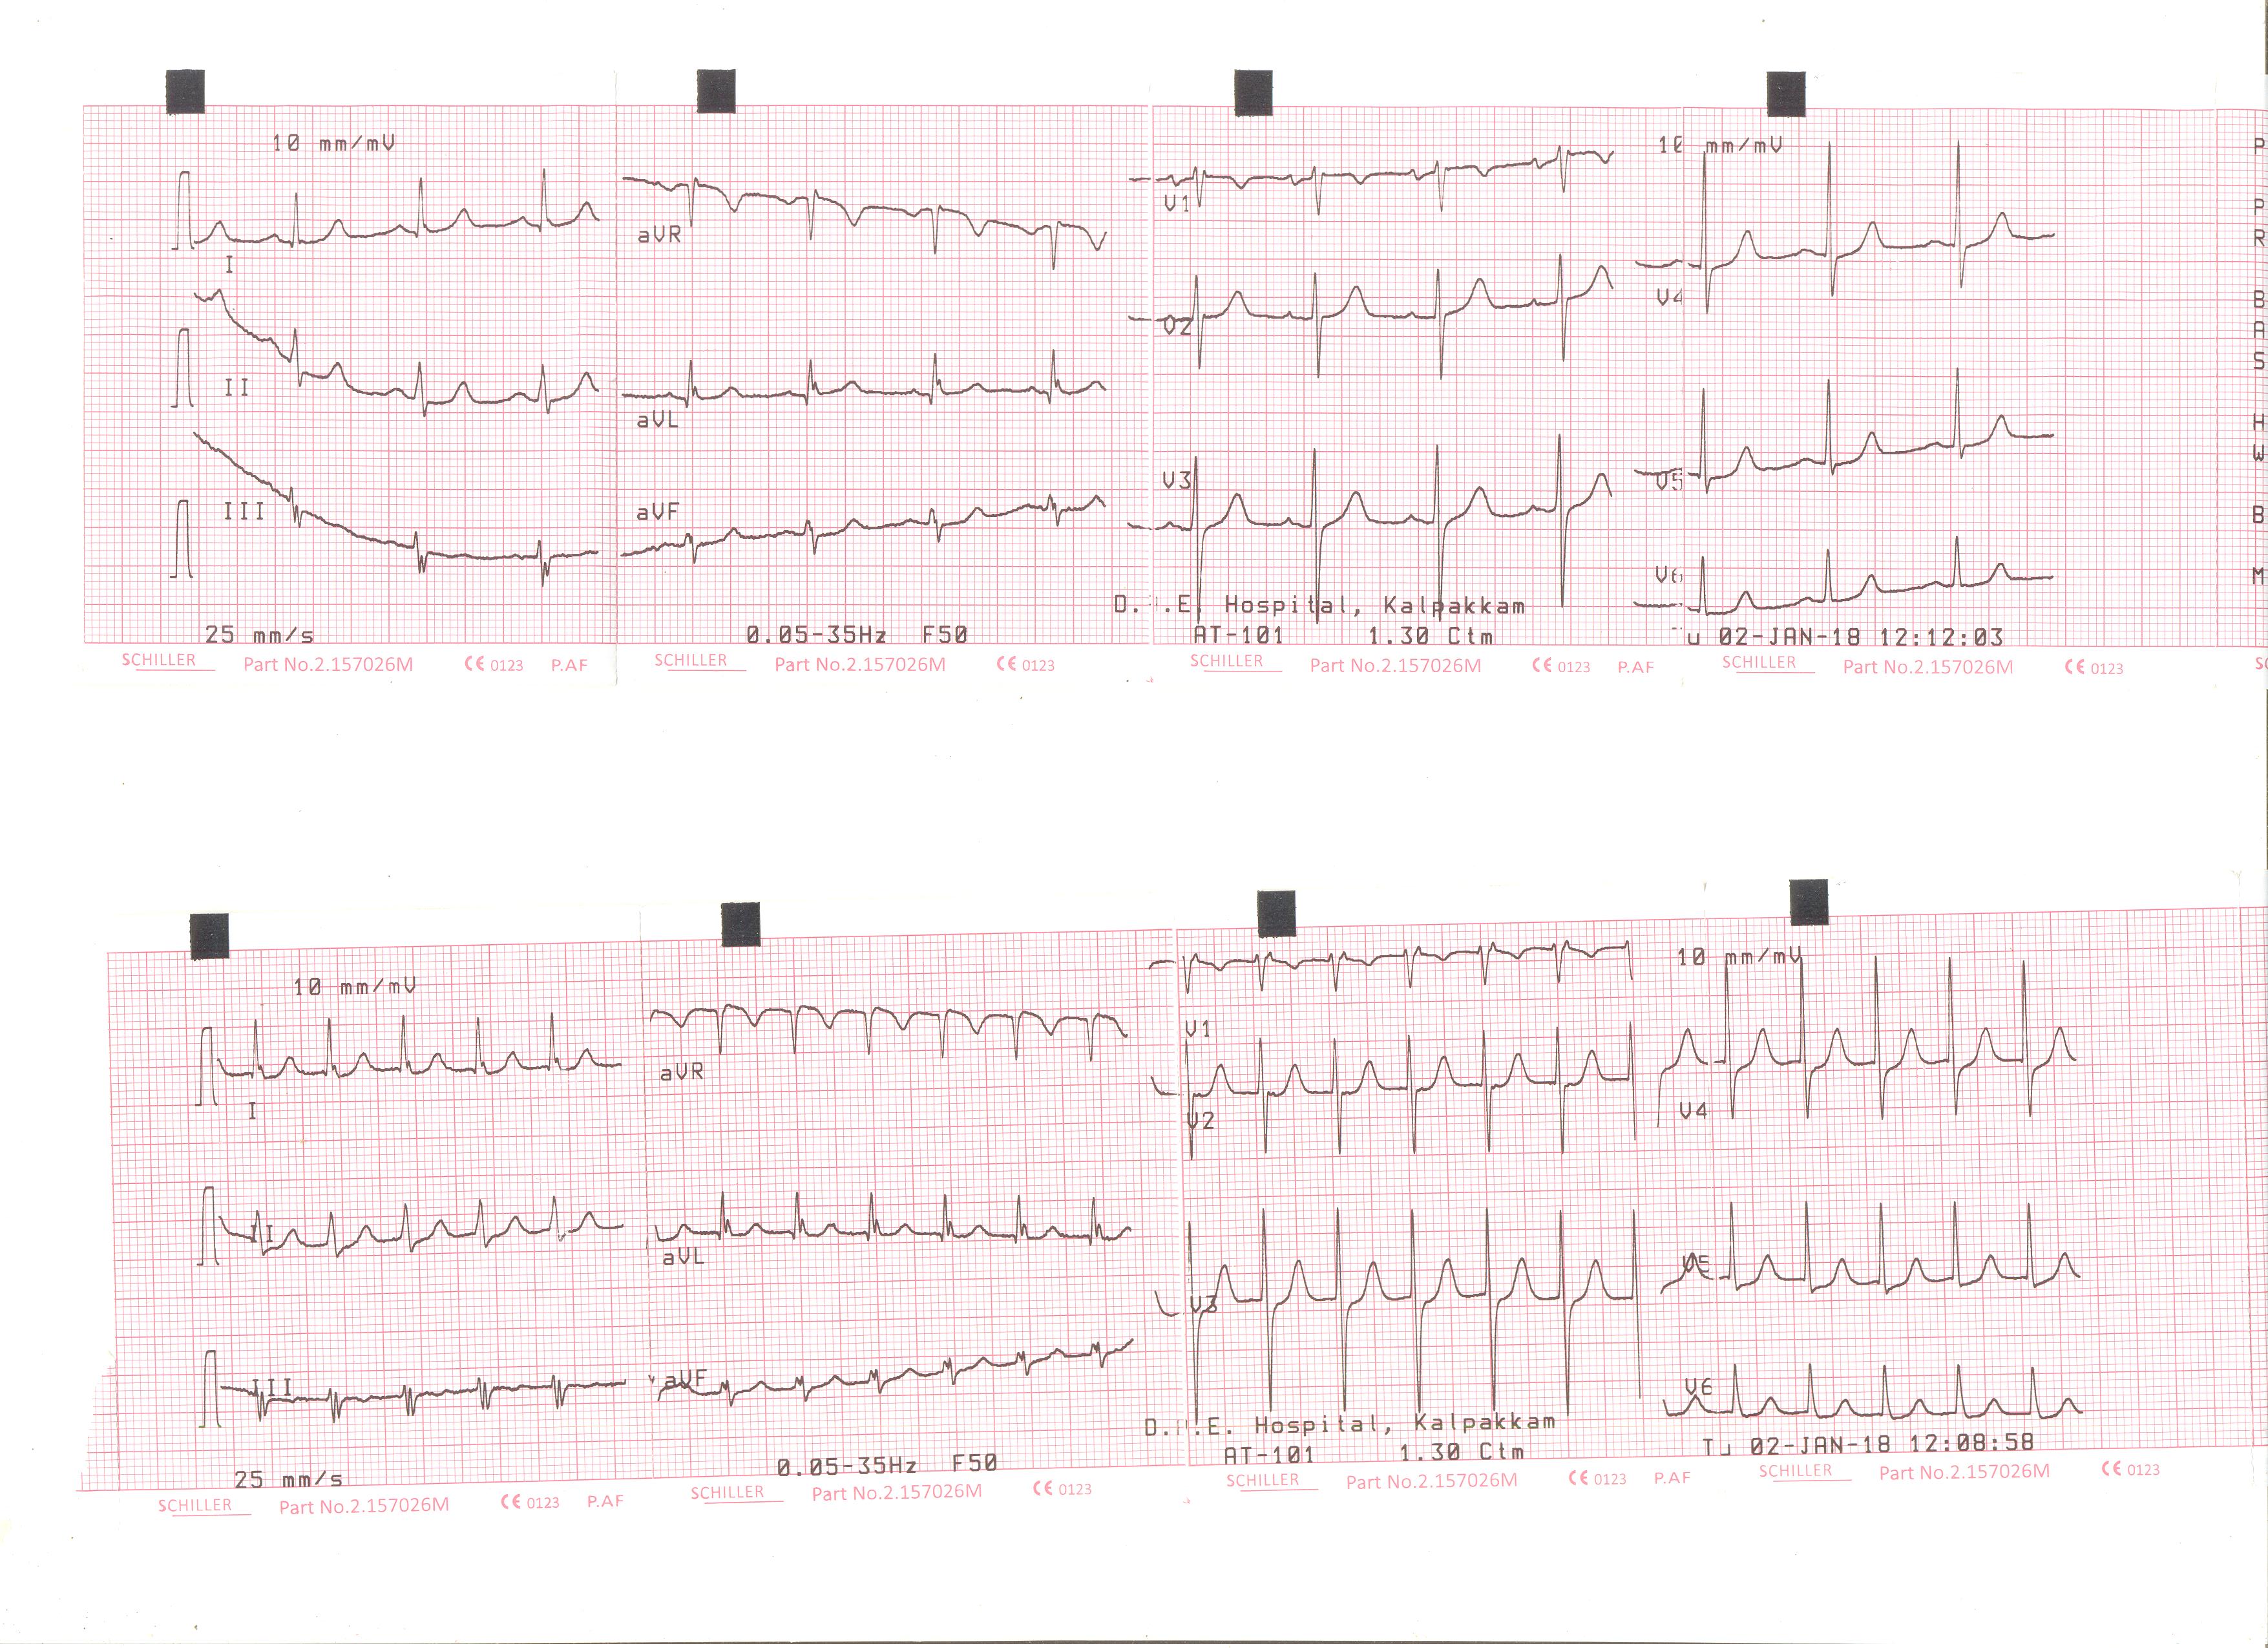

Middle aged male with previous myocardial infarction

pvc.png